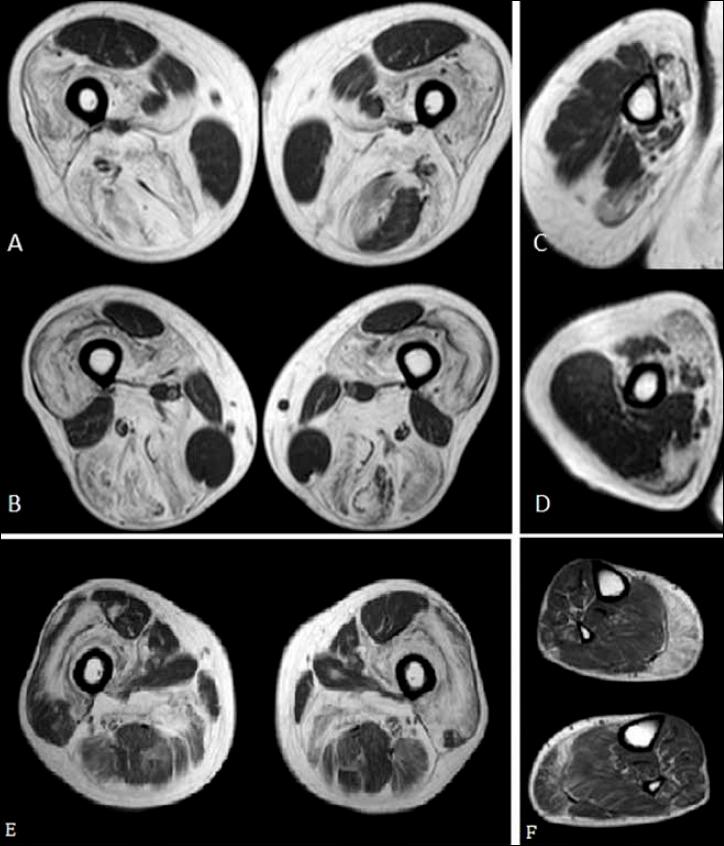

Mutations in gene, encoding merosin, are generally responsible of a severe congenital-onset muscular dystrophy (CMD type 1A) characterized by severe weakness, merosin absence at muscle analysis and white matter alterations at brain Magnetic Resonance Imaging (MRI). Recently, mutations have been acknowledged as responsible of LGMD R23, despite only few cases with slowly progressive adult-onset and partial merosin deficiency have been reported. We describe 5 independent Italian subjects presenting with progressive limb girdle muscular weakness, brain white matter abnormalities, merosin deficiency and gene mutations. We detected 7 different mutations, 6 of which are new. All patients showed normal psicomotor development and slowly progressive weakness with onset spanning from childhood to forties. Creatin-kinase levels were moderately elevated. One patient showed dilated cardiomyopathy. Muscle MRI allowed to evaluate the degree and pattern of muscular involvement in all patients. Brain MRI was fundamental in order to address and/or support the molecular diagnosis, showing typical widespread white matter hyperintensity in T2-weighted sequences. Interestingly these alterations were associated with central nervous system involvement in 3 patients who presented epilepsy and migraine. Muscle biopsy commonly but not necessarily revealed dystrophic features. Western-blot was usually more accurate than immunohystochemical analysis in detecting merosin deficiency. The description of these cases further enlarges the clinical spectrum of -related disorders. Moreover, it supports the inclusion of LGMD R23 in the new classification of LGMD. The central nervous system involvement was fundamental to address the diagnosis and should be always included in the diagnostic work-up of undiagnosed LGMD.

基因突变,编码 merosin,通常负责严重的先天性肌营养不良症(CMD 型 1A),其特征是严重的无力、肌肉分析中 merosin 缺失和大脑磁共振成像(MRI)中的白质改变。最近,基因突变被认为是 LGMD R23 的病因,尽管仅有少数几例报道为缓慢进展的成年发病和部分 merosin 缺乏。我们描述了 5 例意大利独立患者,他们表现为进行性肢体带肌无力、脑白质异常、merosin 缺乏和基因突变。我们检测到 7 种不同的突变,其中 6 种是新的。所有患者均表现为正常的心理运动发育和缓慢进展的无力,发病时间从儿童期到四十多岁不等。肌酸激酶水平中度升高。1 例患者表现为扩张型心肌病。肌肉 MRI 可评估所有患者的肌肉受累程度和模式。脑 MRI 对于明确和/或支持分子诊断至关重要,在 T2 加权序列上显示出典型的广泛白质高信号。有趣的是,这些改变与 3 例出现癫痫和偏头痛的患者的中枢神经系统受累有关。肌肉活检通常但并非总是显示出肌营养不良的特征。Western blot 在检测 merosin 缺乏方面通常比免疫组织化学分析更准确。这些病例的描述进一步扩大了 -相关疾病的临床谱。此外,它支持将 LGMD R23 纳入新的 LGMD 分类。中枢神经系统受累对于明确诊断至关重要,应始终包含在未确诊的 LGMD 的诊断评估中。